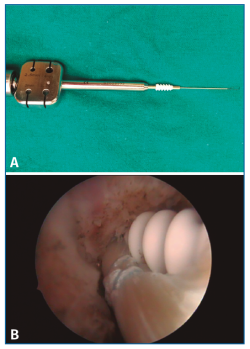

Una vez realizados los 2 túneles, desde el portal anterolateral se inserta el tornillo de biotenodesis de 5 × 15 mm con la plastia colocada hasta la punta del destornillador y se inserta el tornillo siguiendo la técnica (Figura 6).

Figura 6. Tornillo de biotenodesis con la plastia colocada y lista para su introducción.

Una vez colocados los 2 tornillos, se puede objetivar la estabilidad de la plastia intraarticularmente con el artroscopio y externamente con un gentil movimiento varo-valgo (Figura 8).

Figura 8. Plastia una vez realizado el bloqueo a nivel del astrágalo. Resultado final.